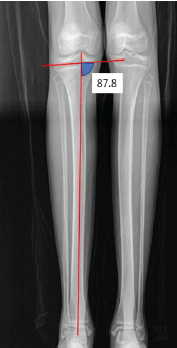

Combined Sulcus Deepening Trochleoplasty, Varus Distal Femoral Osteotomy, and Medial Patellofemoral Ligament Reconstruction for Recurrent Patellar Instability with Trochlear Dysplasia, Genu Valgum, and Medial Patellofemoral Ligament Tear

Sujit Jos , Prannoy Paul , Antony J , Durlav Jyoti Dutta , Samson Samuel , Jerson John Mathew

………………………………p.178-183